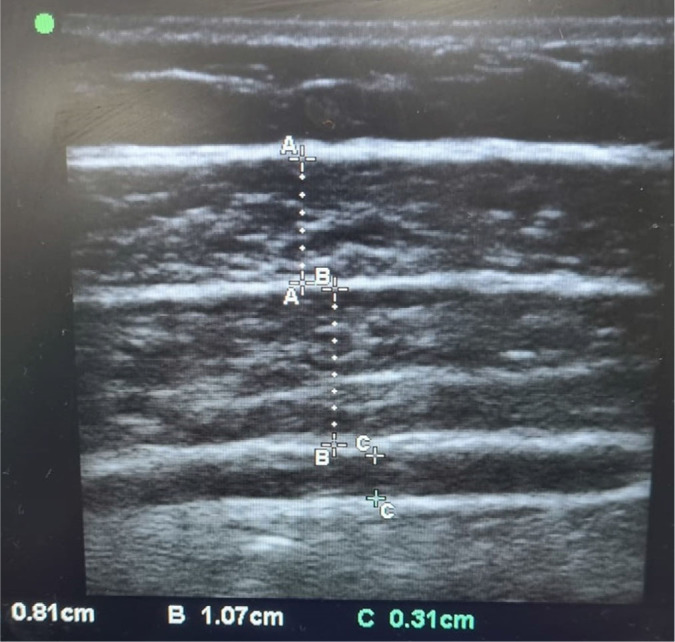

Material and methods: This prospective observational study was conducted at a tertiary liver transplant center between September 2023 and May 2024. USG was used to measure the thickness of the external oblique (EO), internal oblique, and transversus abdominis (TA) muscles in 41 liver transplant recipients and 41 healthy donors. Sarcopenia was also assessed using CT-based L3 skeletal muscle index (L3-SMI) and hand grip strength. Correlations with disease severity (Model for End-Stage Liver Disease, Child-Turcotte-Pugh (CTP)), postoperative outcomes, and ascitic fluid volume were analyzed.

Results: Abdominal muscle thickness was significantly lower in recipients compared to donors (EO: 2.9 ± 1.0 mm vs. 4.5 ± 1.8 mm; TA: 2.2 ± 0.7 mm vs. 3.2 ± 1.0 mm; p <0.001). Sarcopenia prevalence was 78% by L3-SMI and 82.9% by hand grip strength. ROC analysis demonstrated that EO <3.6 mm and TA <2.55 mm predicted sarcopenia in males with high sensitivity and specificity. Muscle thinning correlated with higher CTP scores, greater ascitic fluid volume, and prolonged intensive care unit stay.

Conclusions: USG-derived abdominal muscle thickness, especially EO <3.6 mm and TA <2.55 mm in males, is a reliable, non-invasive marker for sarcopenia in liver transplant candidates. It correlates with disease severity and postoperative morbidity, supporting its utility in pre-transplant risk stratification.